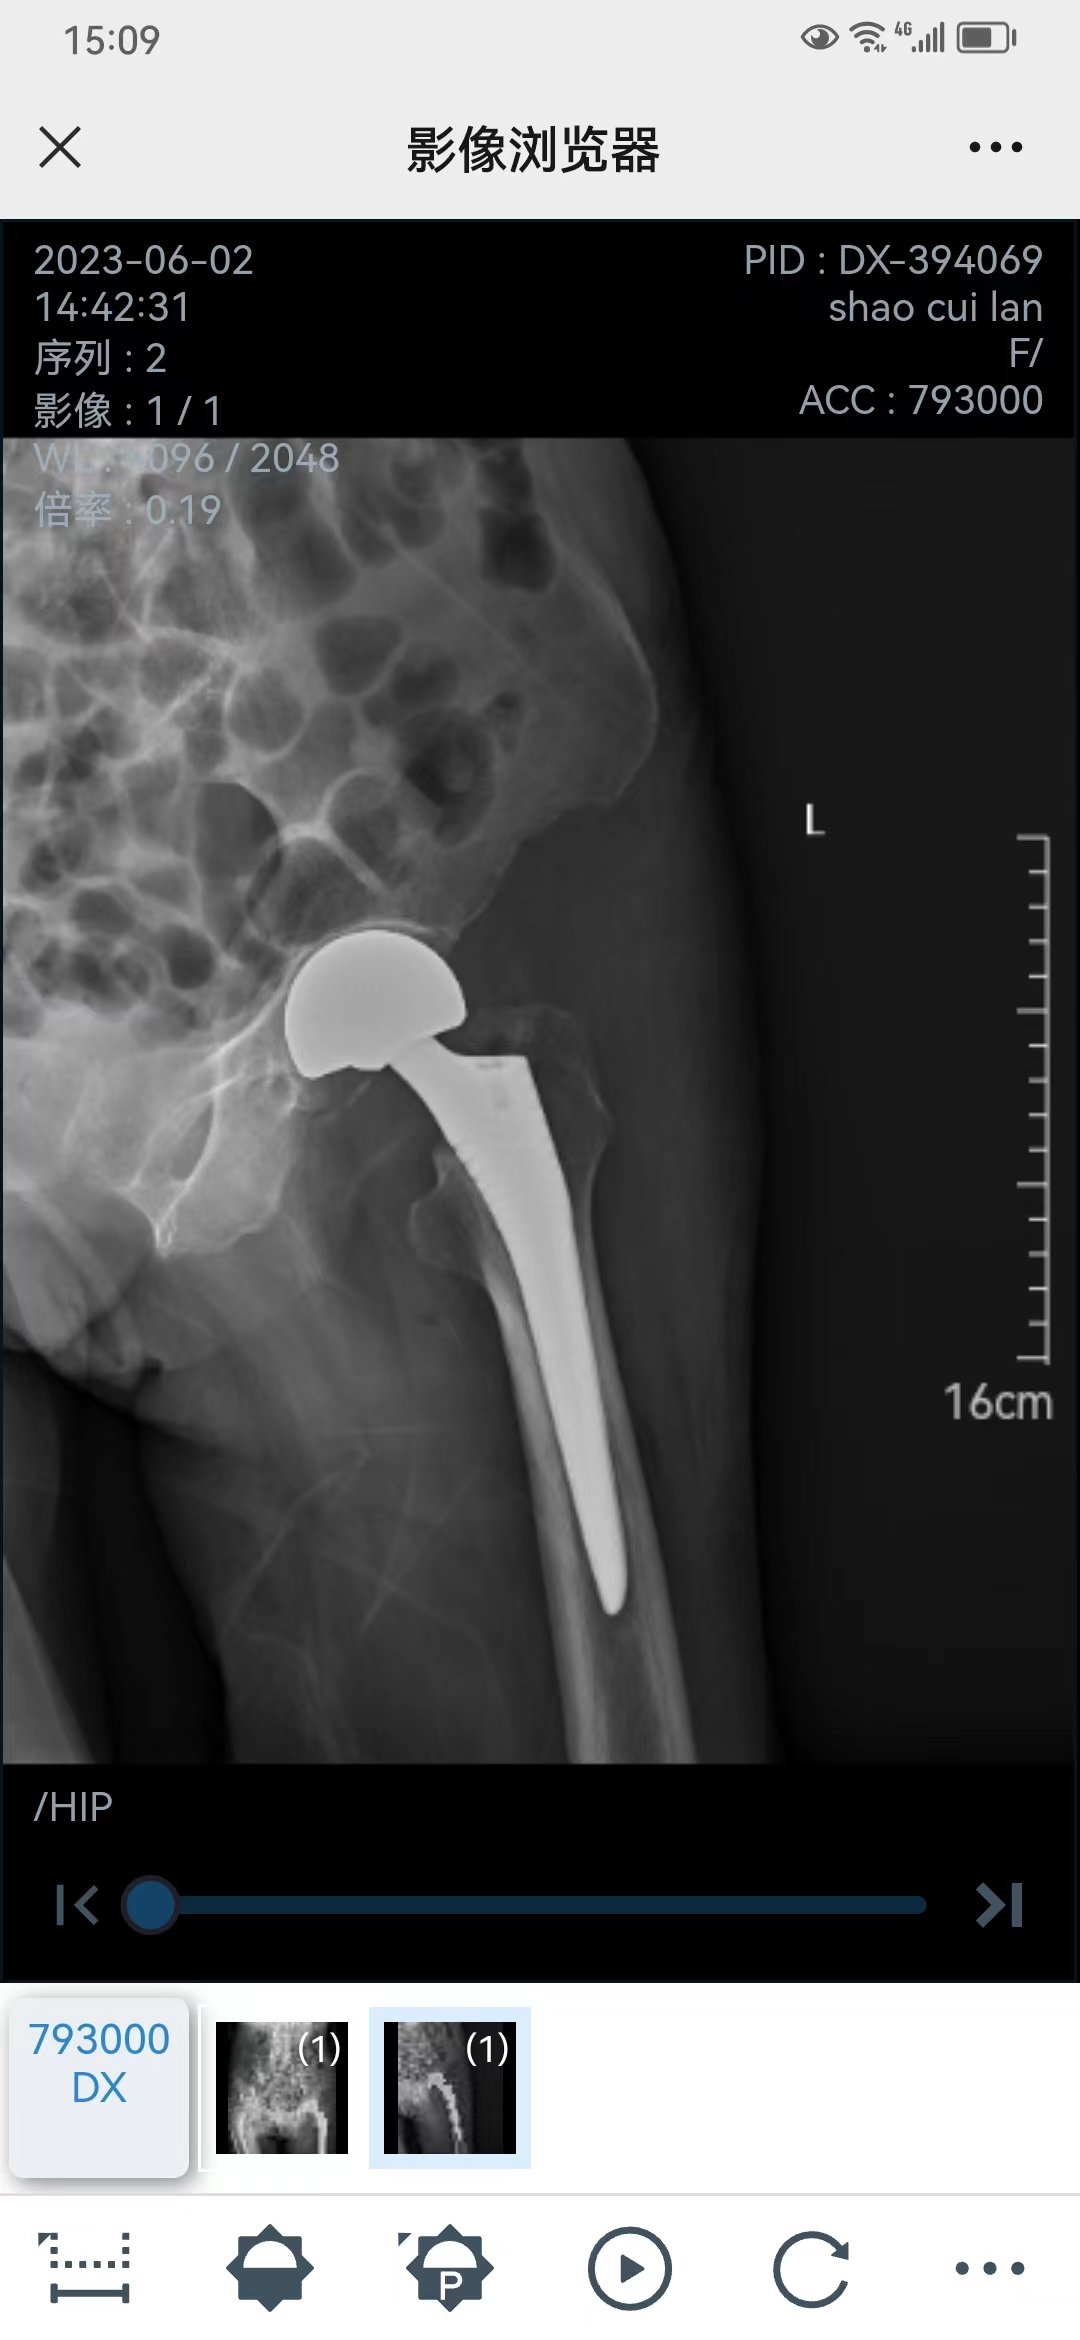

邵奶奶家住灵洞乡洞源村,前一天晚上在家里上厕所不慎跌倒,感觉髋部疼痛,不能行走。急诊经过仔细检查,诊断为左侧股骨颈骨折,入住骨伤科病区。完善入院发现老奶奶同时并发心脏瓣膜病、心房颤动、胸腔积液、高血压病极高危组、中度贫血、血小板减少症,长期口服华法林等情况。

31日,手术如期进行。骨伤科主任蒋晶飞,医师陈瑞芝、黄敬成通力合作,同时邀请了金华市中心医院麻醉科杜光生主任医师为老人麻醉。手术历时20余分钟非常顺利,术中出血很少,整个过程非常平稳。

目前,邵奶奶已经恢复的很好,可以下地行走。